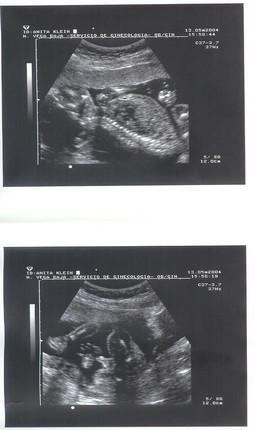

Takido és a többiek, remélem nem haragszotok meg, és nem tartotok idiótának, ha felteszem Szili UH képeit, anno, többek között Csakegy kedvéért is.

Kép

Itt 7 hetes volt, ilyet írtak, hogy embrióárnyék látszik. Hmm, hát Ő nem csak egy árnyék, még ilyet!

Ezt a Sote II-n csinálták, azt mondta az UH-s csaj, hogy milyen szép! Szerintem is, már a pocakban is az volt!

Na és itt már nagyfiúként szopizza az ujjacskáját.

Remélem, hogy jól kivehetők a képek, és tetszenek is!

És azt is remélem, hogy majd a kistesóról is hasonló klassz képek készülnek, ha majd összejönne végre!